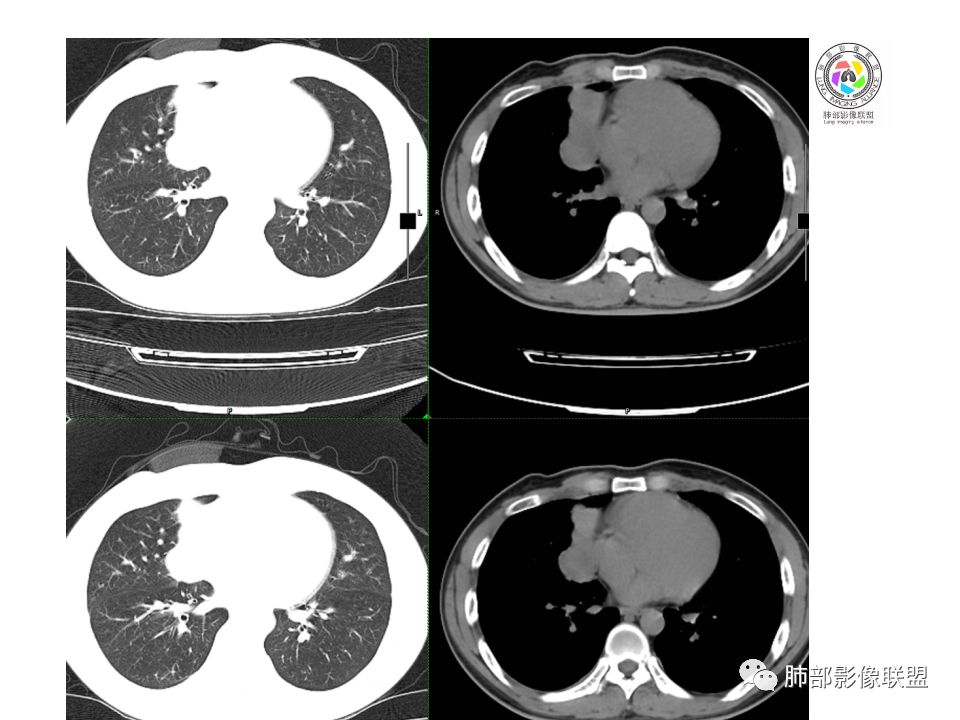

晨读:前纵隔占位,密度不均,沿着右侧纵膈延伸到肺门水平,周围支气管推移,大血管向内推移。临床有重症肌无力,考虑胸腺瘤可能,鉴别淋巴瘤。

右前纵膈肿块,偏一侧生长,形态欠规则,密度不均匀,其内可见小点状钙化,双肺多发小叶中心结节及钙化灶,右侧胸膜增厚(有陈旧性结核可能),青年男性(27岁),没有增强,考虑,1,前纵隔生殖细胞瘤2,精源细胞瘤

右前上纵隔占位,瘤肺交界面清楚,提示纵隔来源,其内有点状钙化,右侧胸腔积液,有临床症状,年龄轻,考虑生殖来源可能,胸腺瘤待排,请结合临床相关检查或CT增强进一步检查。

前纵隔占位,伴点状钙化;上腔静脉后移位。伴右胸膜局限性增厚,临床有重症肌无力,病人年轻,考虑胸腺瘤可能,鉴别生殖源性肿瘤。

右前纵隔占位,有分隔`低密度、点状钙化,边缘光滑,侵袭心包不明确,伴右胸少量积水,考虑恶性,生殖源性可能大,有视物不清,是否脑转移待查。建议HCG丶AFP检查。鉴别1:胸腺瘤、癌,30一40岁以下,少见,但有眼脸下垂,肌无力,待排除。2:淋巴瘤:侵袭性不强,有点状钙化,不支持。3:畸胎瘤:有低密度丶钙化,建议增强进一步明确。4:神经源性:一般后纵隔常见,不支持。5:LCD:症状少见,可以有树枝状钙化,浆细胞型可以有低密度,增强进一步明确

没有增强,好像两个病灶,上方三角形的像是胸腺增生。下方肿块,没有增强显得更难了,微钙化,轻度分叶,像有坏死低密度影,右侧少量胸水,胸膜受侵.,有视物模糊眼睑下垂。考虑胸腺瘤B1型及以上、B2型可能或生殖细胞瘤

前纵隔右区占位性病变,上区与胸腺延续,下区呈分叶状,尽管年龄<30还是首先考虑胸腺瘤,侵袭性可能性大(眼睑下垂不知是否有关)。鉴别主要是生殖细胞类肿瘤,主要是精原细胞瘤。另左肺上叶结核球,右侧胸腔积液,需除外结核性胸膜炎和转移

右前上纵膈肿块,内有点状钙化和少许小片状坏死,局部边界似欠清,右侧胸膜腔少量积液,年轻男性,小于30岁,有重症肌无力,虽然年龄偏轻,仍先考虑胸腺瘤,代排生殖源性肿瘤

晨读前纵隔肿块,偏右侧,密度不均,见点状钙化灶及分隔状低密度影。胸腺瘤>生殖细胞瘤>淋巴瘤

前中纵隔(胸腺癌区)不规则肿块,密度不均,有坏死区、点状钙化,边缘不会整肿块偏向右侧,向心包流注感,右胸腔少量积水。患者27岁,重症肌无力表现。